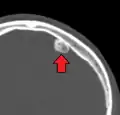

| Osteoma of external auditory meatus | |